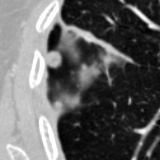

The current study focuses on lung nodule retrieval from a database of CT scans, where patches taken from CT slices of pulmonary nodules are to be mapped into an embedding. LIDC-IDRI [5] is a dataset of thoracic CT scans of 1,010 patients. All the scans were annotated by up to four radiologists, where each one identified, segmented and evaluated separately the lung nodules of a diameter above . Their evaluation also included ratings for a set of 9 characteristics: Subtlety, Internal structure, Calcification, Sphericity, Margin, Lobulation, Spiculation, Texture and Malignancy. The rating system was based on a discrete score of 1-5. Four examples of nodule patches are illustrated in Figure 2: 2 benign (a, b) and 2 malignant (c, d). A rounded vector of the mean rating is bellow each nodule, with the characteristics ordered according to the listing above. The most prominent difference between a and b is the calcification: 3 (solid) and 6 (absent) accordingly. d compared to c has a more defined margin, is more lobulated, but less spiculated. The malignancy score is used to define malignancy classes: score of 1-2 is benign, score of 3 is unknown, and a score of 4-5 is malignant.

(a) Benign

3, 1, 3, 3, 4, 3, 1, 5, 1

(b) Benign

3, 1, 6, 5, 5, 1, 1, 5, 2

(c) Malignant

5, 1, 6, 3, 3, 4, 1, 5, 5

(d) Malignant

4, 1, 6, 3, 4, 2, 2, 5, 4